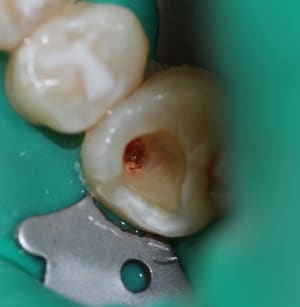

endo1_fye5ff.jpg

Voir le message contenant cette image